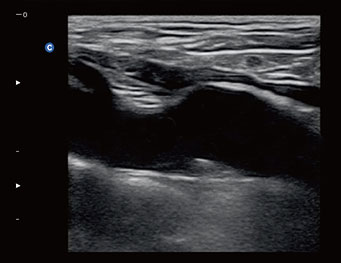

Primary flexor tendon , 2B Mode